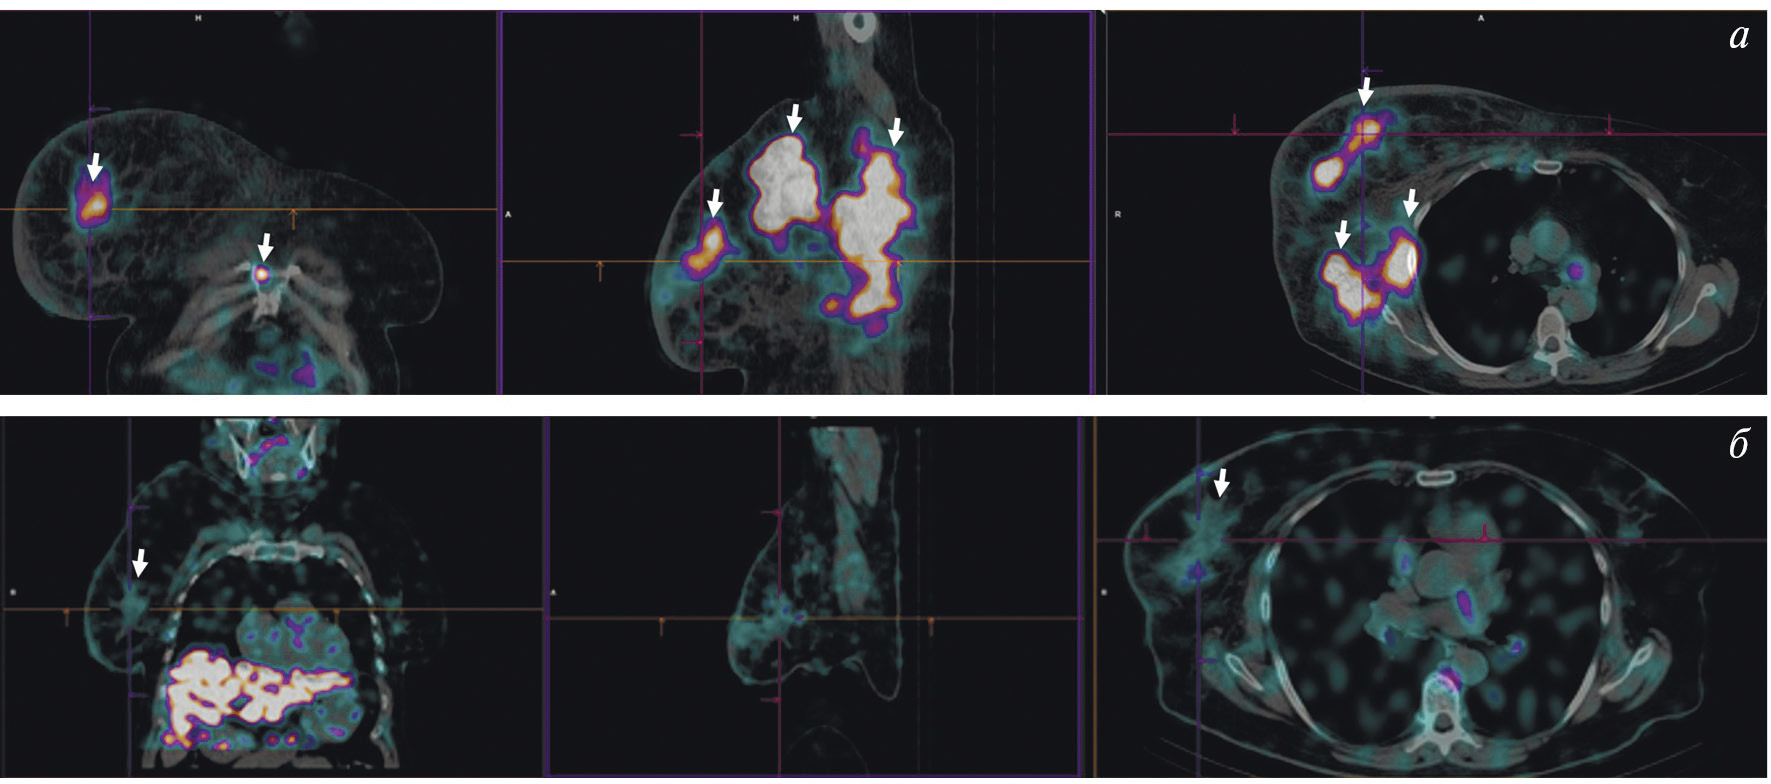

Радиофармпрепарат 99mTc-1-Тио-D-глюкоза и набор для его приготовления разработаны в НИИ онкологии Томского НИМЦ и ТПУ (“Тиоскан, 99mТс”, Россия). Неповреждённый гематоэнцефалический барьер непроницаем для данного препарата, поэтому 99mTc-1-Тио-D-глюкоза хорошо показала себя в диагностике опухолей головного мозга (рис. 7) [43]. Кроме того, ОФЭКТ/КТ с 99mTc-1-Тио-D-глюкозой рекомендована для стадирования и прогноза результатов лечения лимфопролиферативных заболеваний (рис. 8) [44, 45].

Рис. 8. ОФЭКТ/КТ с 99mTc-1-Тио-D-глюкозой пациентки с лимфомой Ходжкина. Стрелками обозначено накопление РФЛП в лимфатических узлах правой аксиллярной области